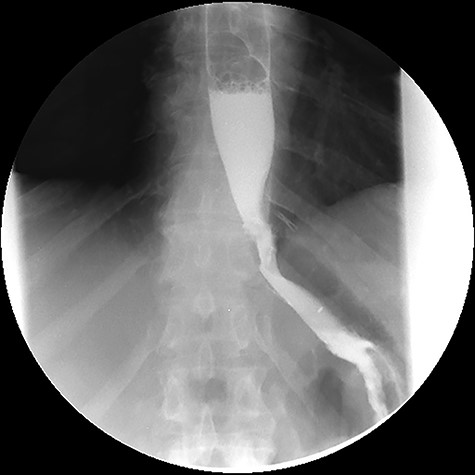

Three months after endoscopic treatment, the patient started complaining of epigastric pain again, without other gastrointestinal symptoms or weight regain. An upper gastrointestinal (GI) contrast swallow study showed recurrence of the GGF and GJA stenosis (see Fig. 4).

Upper gastrointestinal contrast swallow study image where it is possible to see a gastro-gastric fistula with opacification of the excluded stomach.